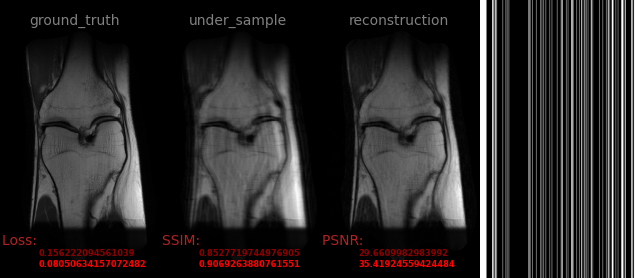

AVS-Net

Image-to-Image

medical